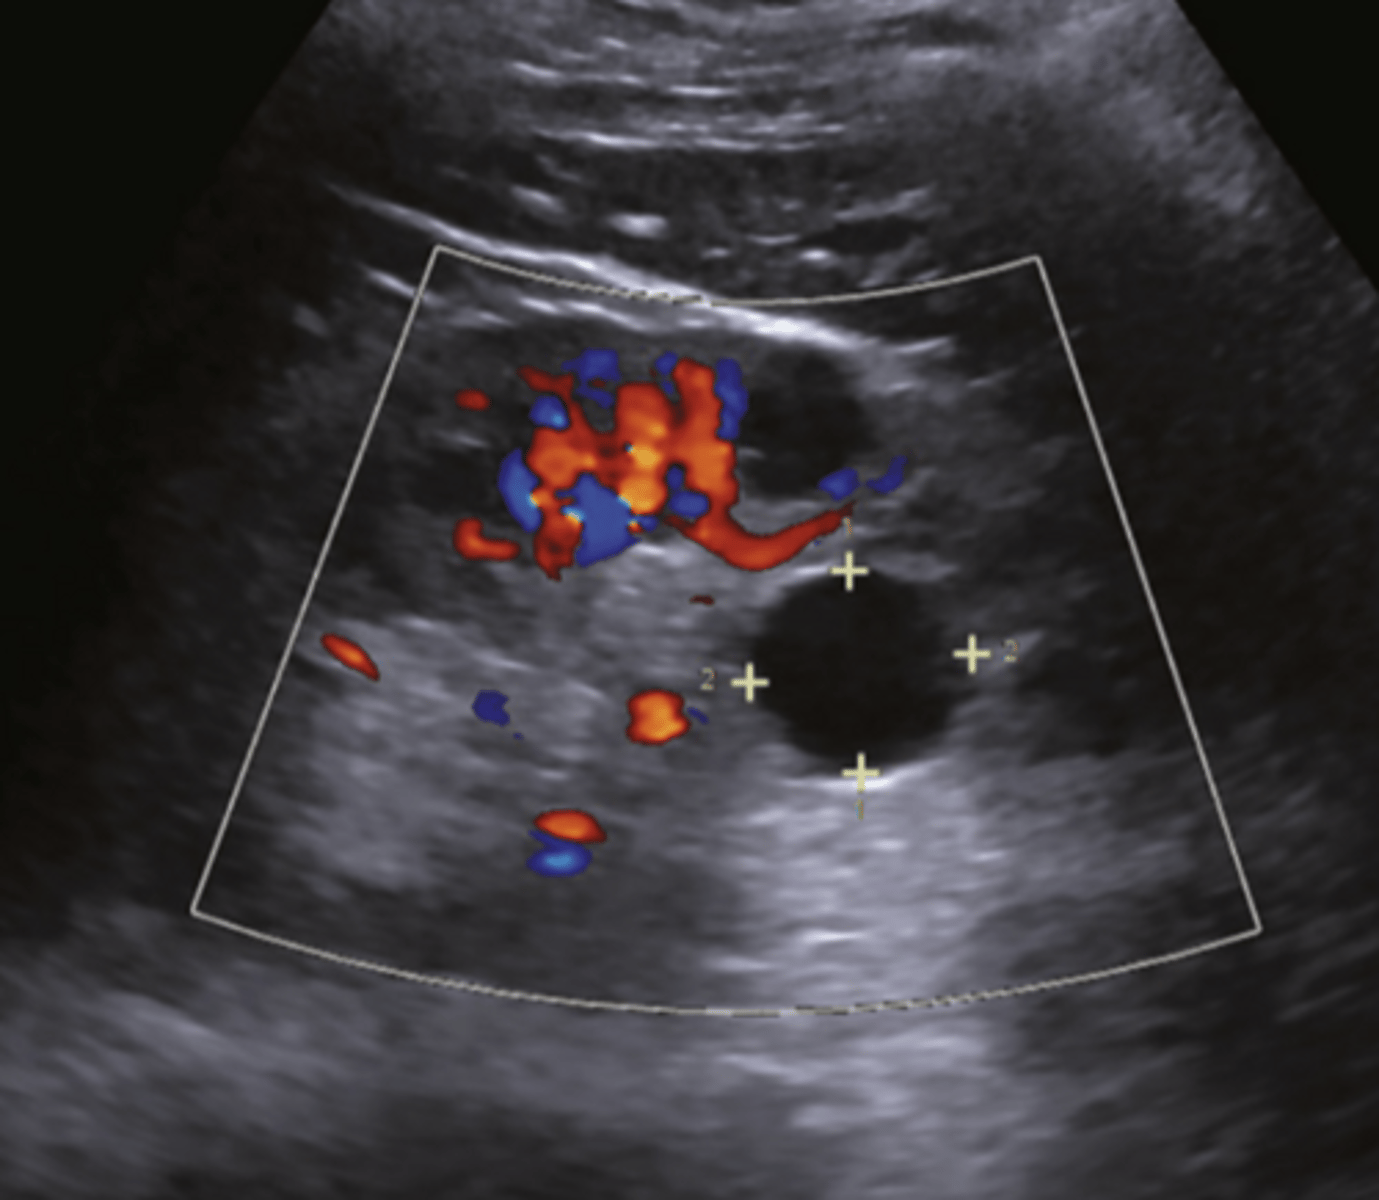

What grade of hydronephrosis is this?

Severe dilatation of the renal pelvis with loss of renal

parenchyma

Grade 3